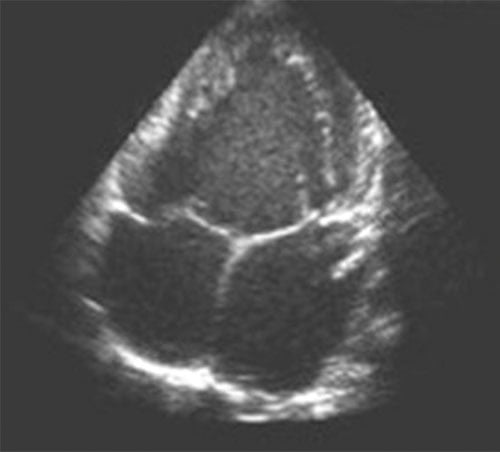

Fig. 11.3 ![]() Ventricule unique : échocardiographie transthoracique, incidence apicale des 4 cavités.

Ventricule unique : échocardiographie transthoracique, incidence apicale des 4 cavités.

Les deux cavités atriales s’abouchent par des valves atrioventriculaires normales et distinctes, dans une seule et même cavité ventriculaire de laquelle naissent l’aorte et l’artère pulmonaire (non visibles sur cette coupe).